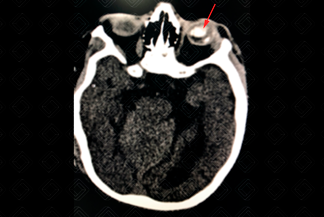

Texto alternativo para a imagem Figuras 1 e 2. Créditos: Dra. Elazir Mota - Rio de Janeiro/RJ

Descrição das figuras 1 e 2: Tomografia computadorizada nos planos axiais. Observam-se os globos oculares de dimensões reduzidas e calcificação grosseira no globo ocular à esquerda (seta na primeira imagem). Há ainda alguns focos tênues de calcificação na interface substância branca-cinzenta (setas na segunda imagem).

• Tomografia computadorizada (TC) do crânio: Quando a ultrassonografia encontra-se alterada, faz-se necessário complementar avaliação com a tomografia. Excelente método para avaliar calcificações grosseiras e aleatórias no parênquima encefálico. Permite ainda avaliação dos globos oculares (e da coriorretinite);